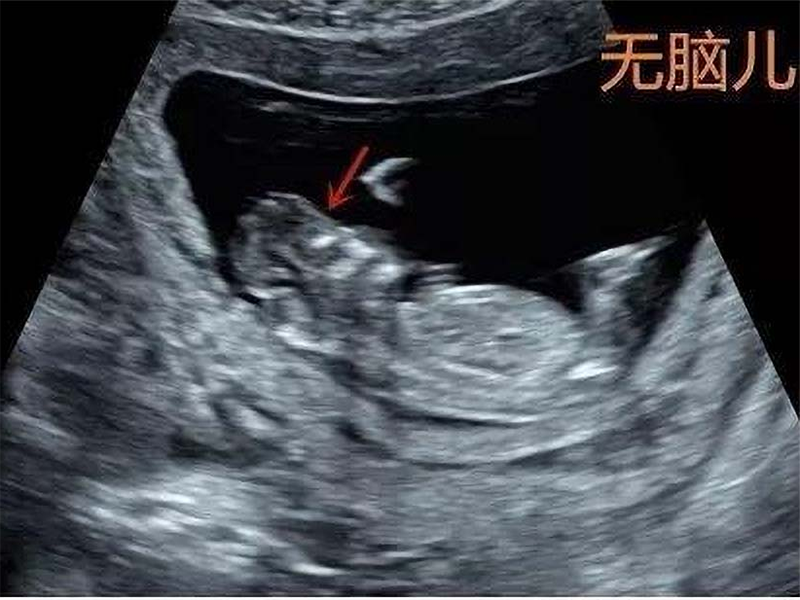

没想到孕12周去照B超的时候,医生却说这个孩子极有可能是有问题的,后来再进行羊水穿刺的时候就发现孩子是无脑儿,只能在医生的建议下进行人流手术。

后来医生详细地询问了圆圆的生活和各方面,判断圆圆因为平时保持身材不怎么吃米饭,也没有备孕,没有补充叶酸,因为严重的叶酸缺乏导致胎儿神经发育受到影响,才会出现无脑儿。